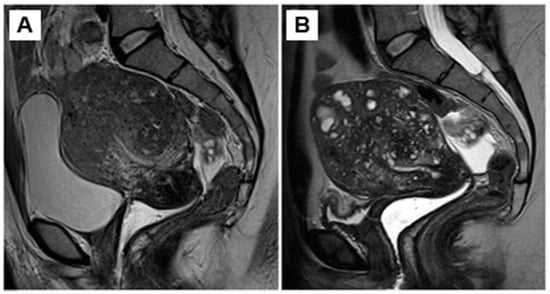

- Donnez, O.; Donnez, J. Gonadotropin-releasing hormone antagonist (linzagolix): A new therapy for uterine adenomyosis. Fertil. Steril. 2020, 114, 640–645. [Google Scholar] [CrossRef]

- Donnez, J.; Donnez, O.; Brethous, M.; Bestel, E.; Garner, E.; Charpentier, S.; Humberstone, A.; Loumaye, E. Treatment of symptomatic uterine adenomyosis with linzagolix, an oral gonadotropin-releasing hormone receptor antagonist: A pilot study. Reprod. Biomed. Online 2021. [Google Scholar] [CrossRef]